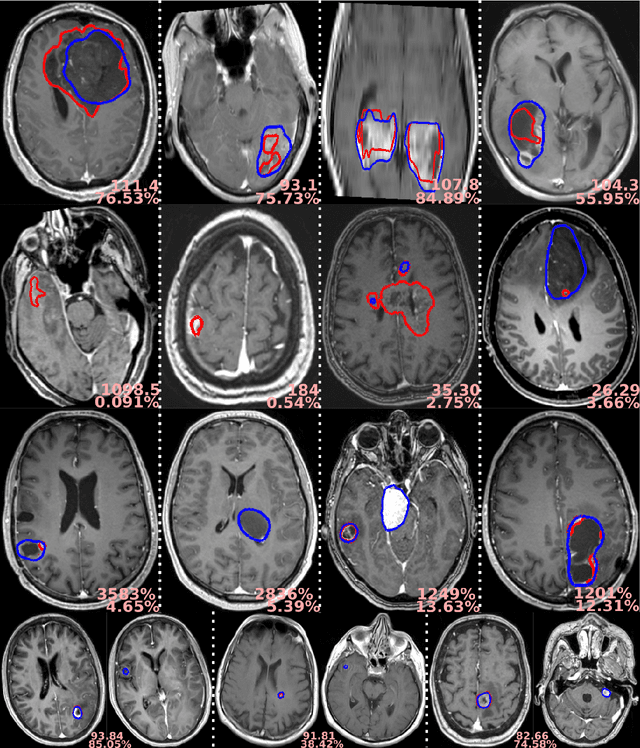

Abstract:For patients suffering from brain tumor, prognosis estimation and treatment decisions are made by a multidisciplinary team based on a set of preoperative MR scans. Currently, the lack of standardized and automatic methods for tumor detection and generation of clinical reports represents a major hurdle. In this study, we investigate glioblastomas, lower grade gliomas, meningiomas, and metastases, through four cohorts of up to 4000 patients. Tumor segmentation models were trained using the AGU-Net architecture with different preprocessing steps and protocols. Segmentation performances were assessed in-depth using a wide-range of voxel and patient-wise metrics covering volume, distance, and probabilistic aspects. Finally, two software solutions have been developed, enabling an easy use of the trained models and standardized generation of clinical reports: Raidionics and Raidionics-Slicer. Segmentation performances were quite homogeneous across the four different brain tumor types, with an average true positive Dice ranging between 80% and 90%, patient-wise recall between 88% and 98%, and patient-wise precision around 95%. With our Raidionics software, running on a desktop computer with CPU support, tumor segmentation can be performed in 16 to 54 seconds depending on the dimensions of the MRI volume. For the generation of a standardized clinical report, including the tumor segmentation and features computation, 5 to 15 minutes are necessary. All trained models have been made open-access together with the source code for both software solutions and validation metrics computation. In the future, an automatic classification of the brain tumor type would be necessary to replace manual user input. Finally, the inclusion of post-operative segmentation in both software solutions will be key for generating complete post-operative standardized clinical reports.